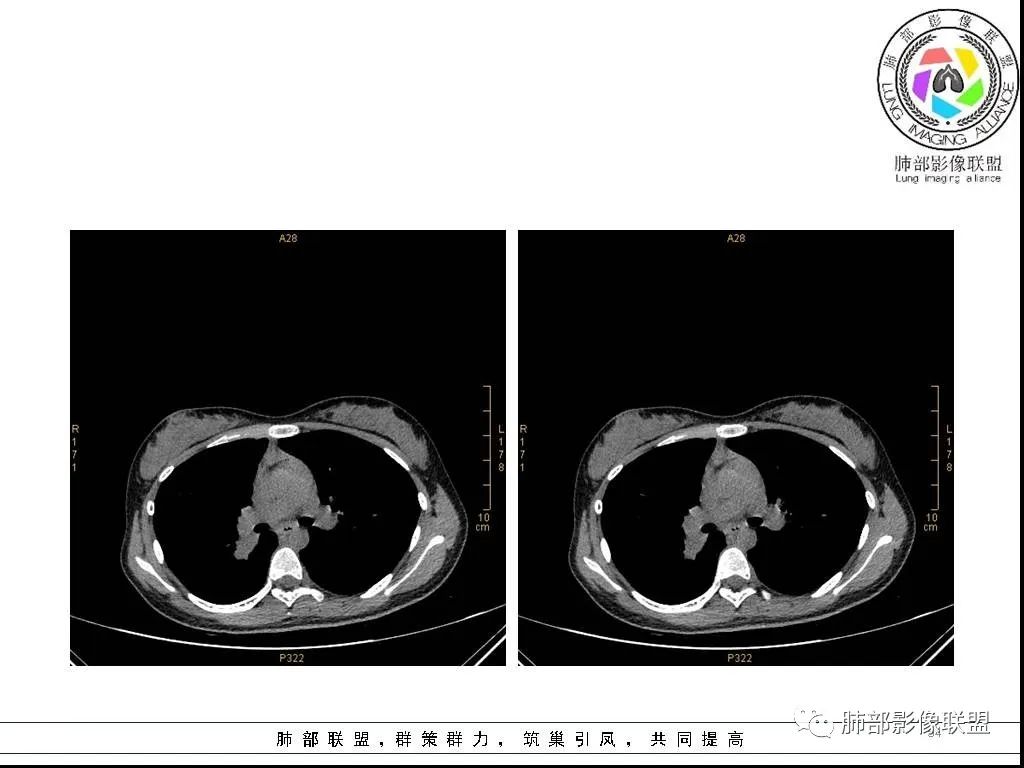

右肺炎症性病变1例CT影像讨论

年轻女性,病程长,咳嗽少痰4个月,辅检未见特殊,CT:右肺团块影,跨叶,主体在下叶背段,外大内小,边缘以膨隆为主,部分平直内收,深分叶,周围有模糊晕,可疑卫星灶,胸膜增厚,糊墙,支气管近端部分进入,粘液栓,有坏死空腔,内壁光整,部分血管侵蚀,强化不均,延迟,明显;同侧R10、7、R4淋巴结肿大,考虑肉芽肿炎,结核,需要与肿瘤鉴别:16岁,女性,诊断肿瘤需要勇气,跨叶多见于炎性,需要进一步活检。

16岁女性,咳嗽,咳痰4月,无发热,白细胞不高,炎性指标(CRP,PPT)不高,血沉增高(75mm/h)。影像表现:右肺胸膜下不规则肿块影,边缘平直,U型凹陷,桃尖征为主,纵隔窗部分层面似有多个结节融合感,近端支气管扩张,堵塞,局部呈鬼脸样改变。边缘可见长短不一毛刺影,周围见晕征,远端见多个小结节卫星灶。胸膜大面积反应性增厚,增强后不均匀中度渐进性强化,局部干酪样坏死可能(CT值-32~-15)内部血管走行较正常,破坏不明显。 医学百科网 | YxBaike.Com

这个病例的特点:病灶贴近斜裂内侧区域,范围较大,直达肺门区。右肺上叶,前、尖、后段前移,病灶嵌塞于上叶后段支气管的后下方区域,未能跟踪到病灶与叶段支气管关系。应当怀疑有额外的支气管存在,也就是副叶。因为这么大的病灶,这么粗大肺动脉进入,伴行的支气管应当比较粗大,但是没能观察到较大的支气管与其相延续。

病灶收缩、跨叶,应当想到存在有畸形的、发育异常的叶裂,一个副叶的病变。这个病灶明显在后段下方,斜裂的上方,靠近肺门侧的叶裂显示不是很清楚,这个应该是副叶来的,不是后段的分支。

病灶内部存在管状分布液性低密度区,这与复查显示的柱状管样气腔对应吻合,支持先天性支气管扩张的存在,仅仅是影像未能显示出入口。

炎性病变的诊断当无异议。患者疗效颇佳,除抗生素覆盖合理外,推测与支气管引流改善密切相关! 医学百科网 | YxBaike.Com

因取材有限,病理意见不够完善和全面,并且未能取得病原学证据。病灶亦不支持一般意义上的肉芽肿病变。